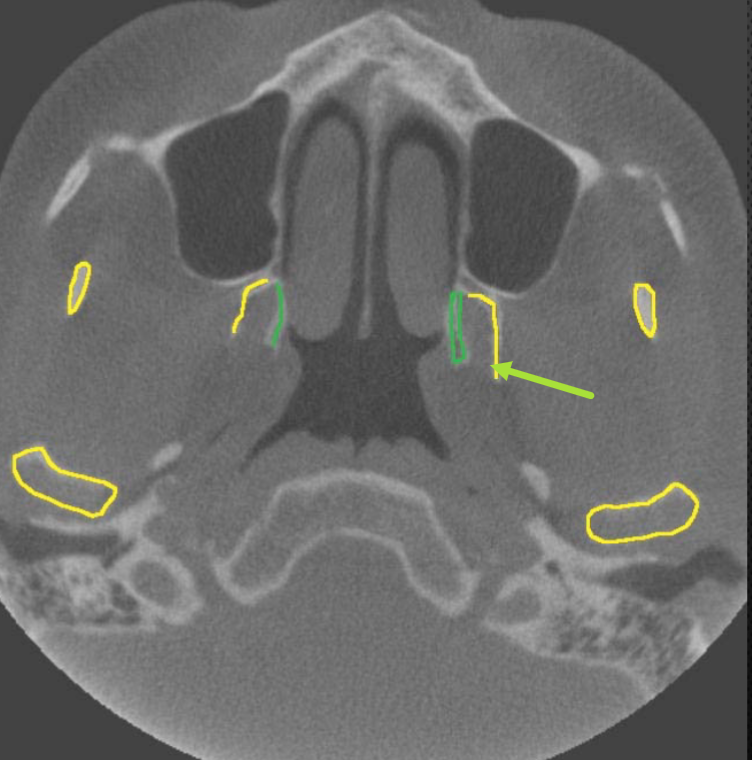

axial

what plane is this

level of maxilla (above maxillary teeth)

at what level is this

maxillary sinus

what is indicated by the GREEN dot

ostium (of maxillary sinus)

identify the structure

uncinate process

identify structure